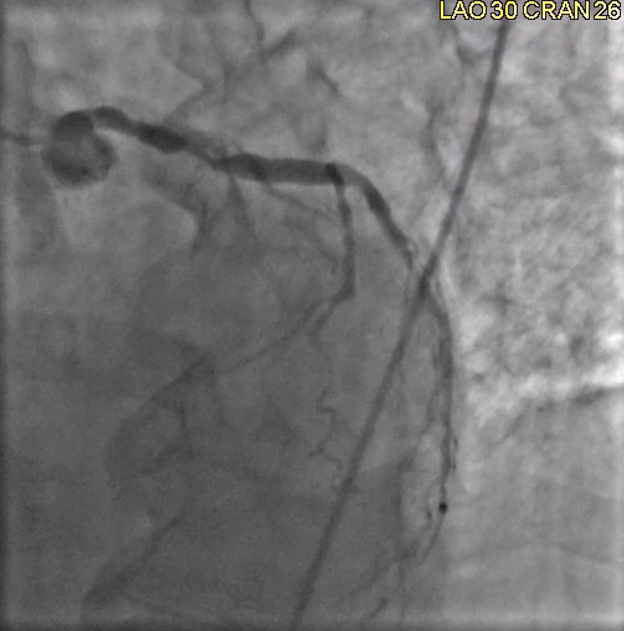

A left heart catheterization revealed a pattern of apical ballooning consistent with stress cardiomyopathy (Figure 2) and a severely depressed left ventricular ejection fraction of 10%. Significant obstructive triple-vessel coronary artery disease was noted with poor collateral circulation (Figures 3-4). No evident left ventricular outflow obstruction. An intra-aortic balloon pump (IABP) was placed, while coronary interventions were held at that time. On the second day of hospitalization, the patient developed intermittent high-grade AV block with hemodynamic instability which progressed to persistent complete heart block (CHB) (Figure 5). Medical management and transcutaneous pacing were initiated until transvenous pacing was achieved. The IABP was later exchanged for an Impella device due to refractory cardiogenic shock and worsening vasopressor requirements.

Figure 4. Left anterior oblique view showing severe stenosis at the ostium of LAD.